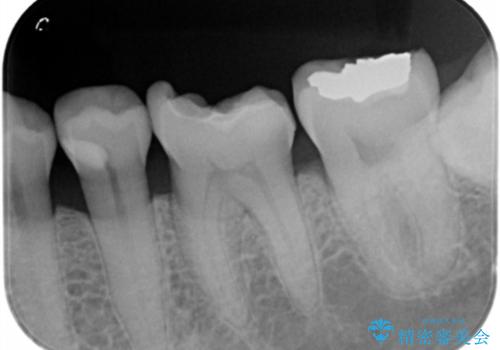

- 奥歯の銀の詰め物が取れたとの事で来院。

詰め物の下に虫歯ができて銀歯が取れてしまった事が予想されます。

白い詰め物でやり直しをしても歯質が薄くなり割れてしまうリスクがあるために、

割れるリスクの少ないジルコニアクラウンにて治療しました。